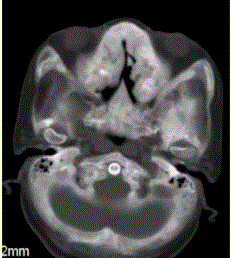

问题 患者女,25岁,左侧面部肿块,突眼10余年。CT表现如下图。 骨纤维异常增生症常需鉴别的疾病有

选项 A.非骨化性纤维瘤 B.嗜酸细胞肉芽肿 C.甲状腺功能亢进 D.成骨性转移 E.巨细胞瘤 F.动脉瘤样骨囊肿

答案 ABD

解析 ABD